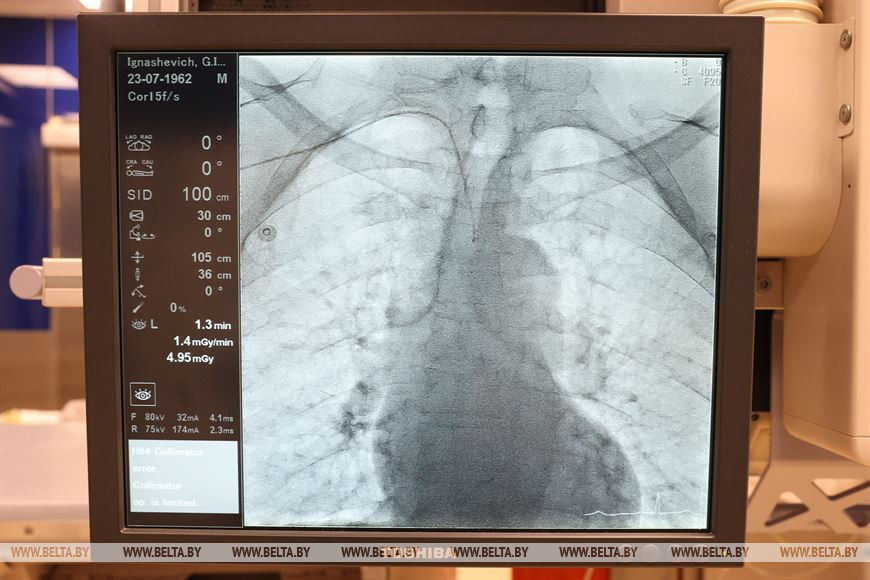

"Солигорская центральная районная больница является одним из четырех межрайонных центров Минской области. В нашем составе функционирует 26 межрайонных отделений и кабинетов. Мы обслуживаем Солигорский район с 128,4 тыс. населения, из них чуть более 109 тыс. - это городские жители, чуть более 18 тыс. - сельские. Также мы оказываем помощь пациентам из семи закрепленных за нами районов Минской области, это практически все районы юга Минской области. Среди них Клецкий, Копыльский, Несвижский, Слуцкий, Стародорожский, Любанский районы. По этим районам мы являемся центром по оказанию высокотехнологичной медицинской помощи, в первую очередь пациентам с острым коронарным синдромом - с инфарктом миокарда, с острым нарушением мозгового кровообращения. Работаем в круглосуточном режиме. В состав центра входит кардиологическое отделение для пациентов с инфарктом миокарда, отделение для пациентов с острым нарушением мозгового кровообращения, кабинет компьютерной магнитно-резонансной томографии и отделение интервенционной радиологии. Мы оказываем помощь на высоком уровне, это было отмечено мониторинговой группой, а также свидетельствуют награды, которые получают наши специалисты. Например, в этом году наш кабинет интервенционной радиологии получил награду "Прорыв года", - рассказал главный врач Солигорской ЦРБ Александр Кисель.

Рентгенэндоваскулярный хирург, заведующий кабинетом ангиографии и руководитель Южного межрайонного центра Минской области Александр Янукович гордится тем, что его отделение, став в 2014 году первым отделением районной эндоваскулярной хирургии в стране, сейчас является крупным специализированным центром. "Мы выполняем практически весь спектр вмешательств, который можно предложить пациентам на уровне районной больницы. Мы - это большой сплоченный коллектив, работающий уже 9 лет. У нас оказывается помощь пациентам южной части Минской области, а это 360 тыс. населения. Основная наша задача - оказание помощи пациентам с ишемической болезнью сердца, с ишемическим инсультом и цереброваскулярными болезнями. Мы также являемся межрайонным центром по имплантации электрокардиостимуляторов, этой программой занимаемся в течение последних двух лет. Прооперировано уже порядка 150 пациентов. Они обслуживаются у нас же - на базе центра организован кабинет контроля кардиостимуляторов. Также с гордостью мы можем сказать, что являемся единственным центром районного уровня в стране, который выполняет вмешательства по ишемическому инсульту, вмешательства на сосудах шеи. Кроме того, являемся межрайонным центром по сосудистой хирургии. Поэтому мы многофункциональная, многопрофильная, многоуровневая структура. Например, сегодня у нас 6 плановых операций, две из них - это постановка кардиостимулятора, три пациента с ишемической болезнью сердца, один из них готовится к кардиологическому вмешательству в РНПЦ кардиологии, два - с перенесенным в прошлом инфарктом. В любой момент к нам могут доставить пациента с ишемическим инсультом, например, а это уже нейрохирургическая помощь. В среднем за сутки мы обслуживаем 10 пациентов. С нового года через нас прошло уже порядка 900 пациентов, и такими темпами за год мы получим цифру в 1-1,6 тыс. пациентов", - рассказал Александр Янукович.